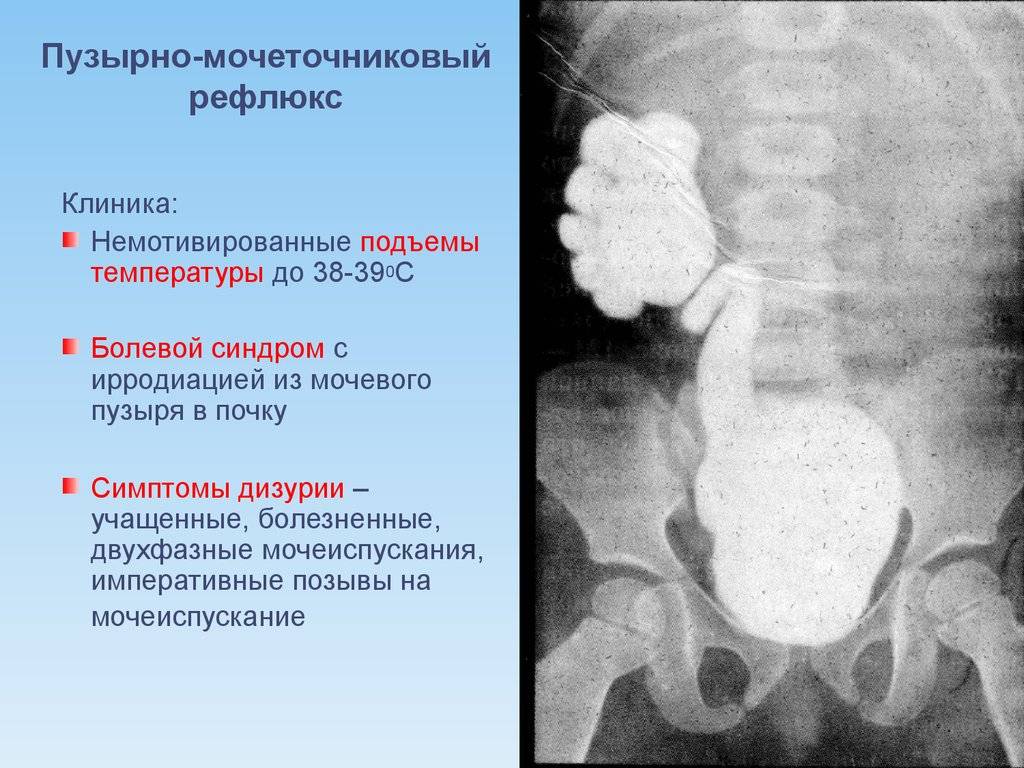

Рефлюксирующий мегауретер: Визуализация и медицинские изображения